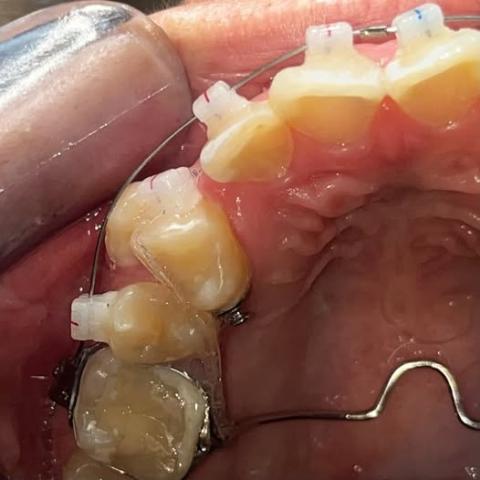

The image shows the upper and lower front teeth with visible brown enamel defects and decay on the upper incisors. There is also visible misalignment and plaque accumulation.

Pain reported by the client is consistent with the visual findings.